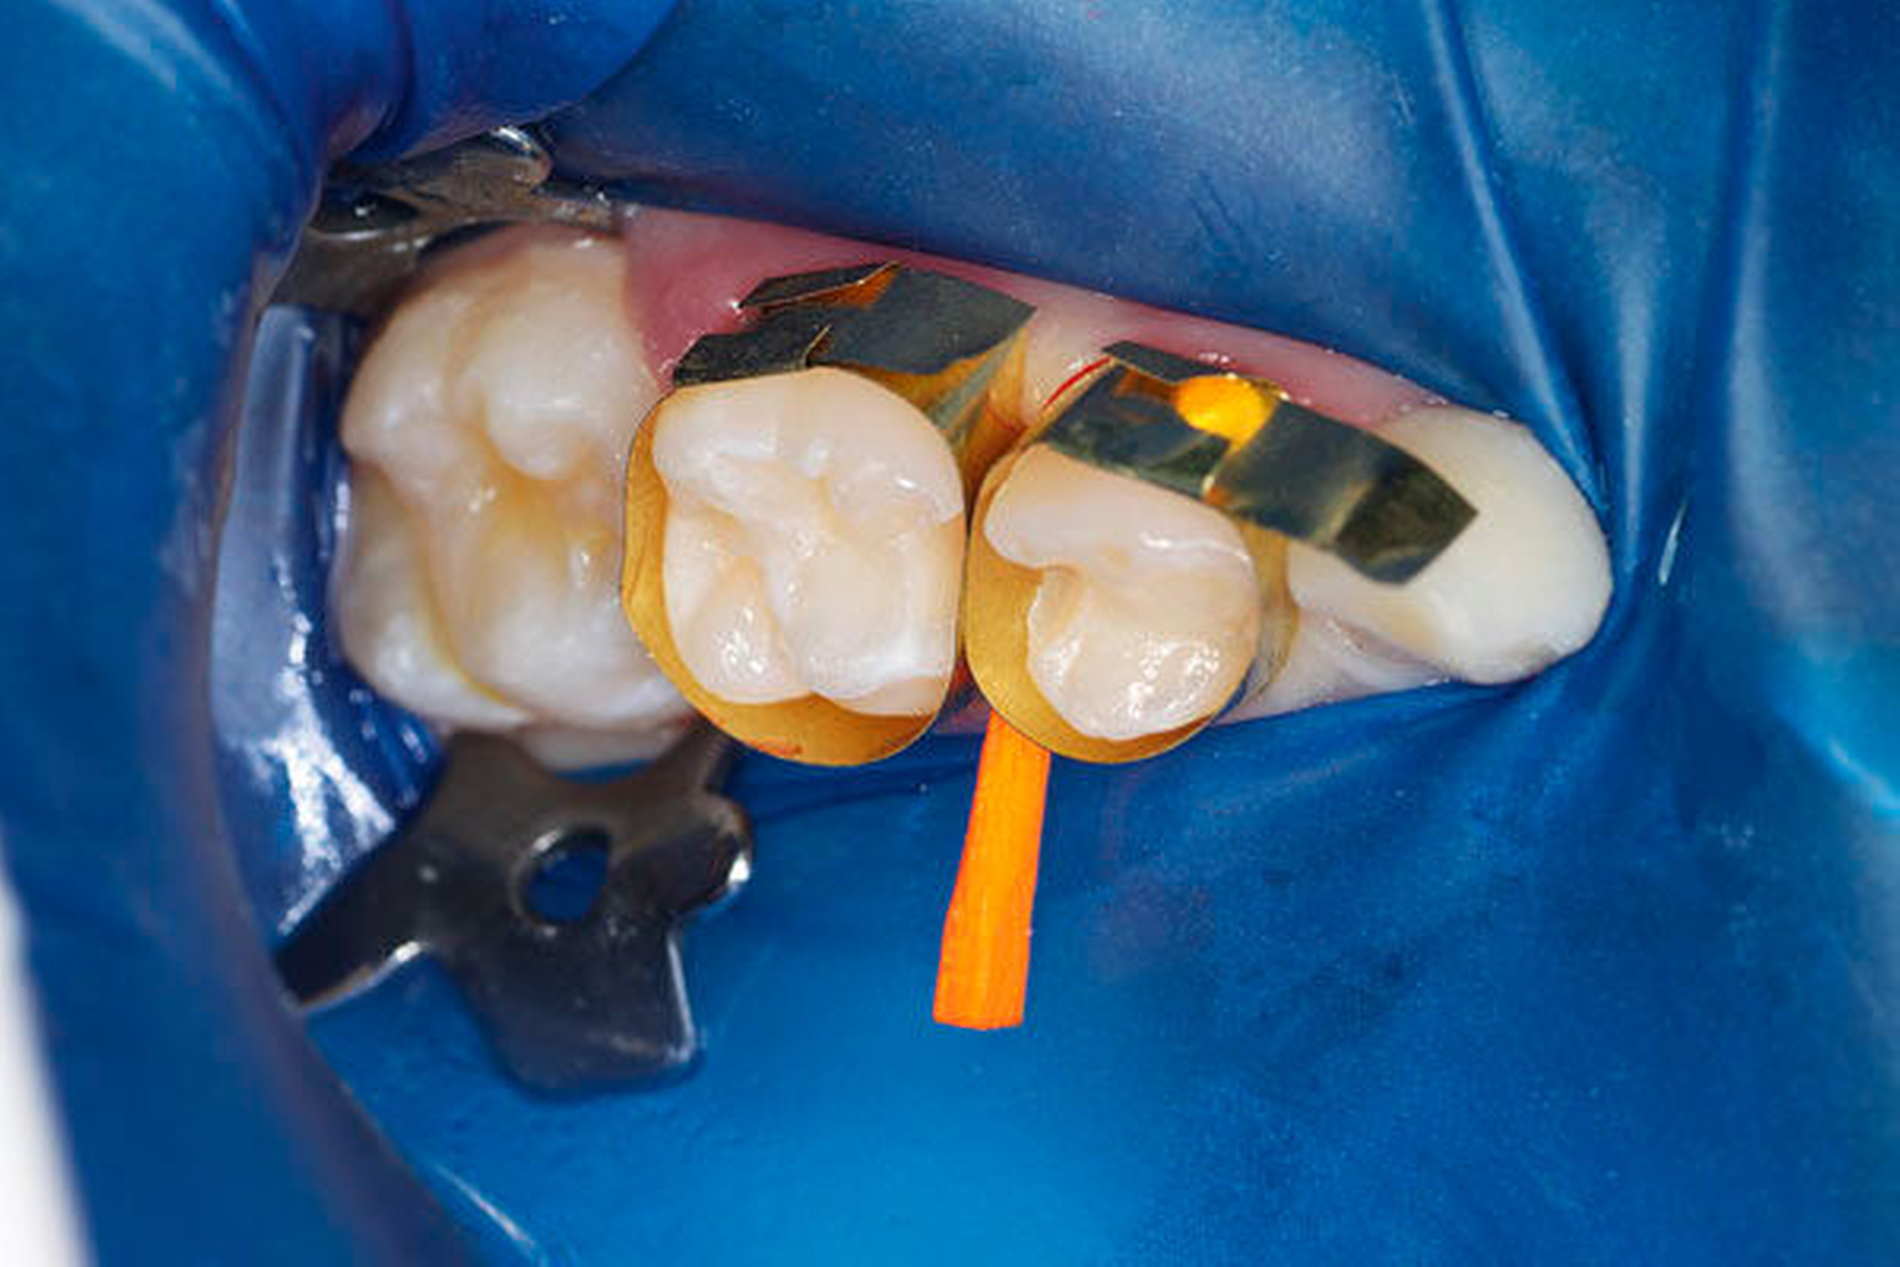

Somit ist die konventionelle Füllungstherapie am Milchmolar, vorzugsweise mit lichthärtendem Glasionomerzement oder Komposit, nur bei kleinen maximal zweiflächigen Kariesdefekten mit ausreichender Dentinschichtstärke zur Pulpa sinnvoll. Da der Milchzahnschmelz auch eine geringere Mineralisation mit aprismatischen Bereichen und größerem Porenvolumen aufweist, ist er schlechter anätzbar [Van Waes und Stöckli, 2001]. Zudem wird durch die reduziertere Schmelzdicke der adhäsive Verbund zwischen Zahnhartsubstanz und Komposit verringert. Bei der Füllungsgestaltung ist ein kinderfreundliches Matrizensystem, beispielsweise die T-Band-Matrize (Pulpdent, USA) ohne Matrizenhalter, empfehlenswert. Im Zuge der Quadrantensanierung lassen sich zwei angrenzende approximale Kavitäten bei guter Verkeilung problemlos füllen, ohne auf einen straffen Kontaktpunkt verzichten zu müssen (Abbildung 5). Dieses Vorgehen spart Zeit und findet bei den Kindern gute Akzeptanz. Die Anschaffung des erforderlichen Instrumentariums lohnt sich auch als Anschaffung für die allgemeinzahnärztliche Praxis.